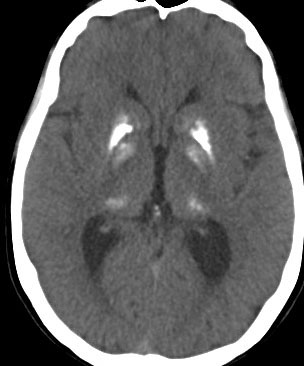

1985年,17才のときに松果体ジャーミノーマで全脳照射45グレイ,18分割,1回2.5グレイの放射線治療を受けました。照射後の数年は普通に社会復帰ができていたということで,大学を卒業し,就職もしていました。しかし,20代後半くらいから認知機能低下(高次脳機能障害)が目立つようになりました。41才で脳幹部梗塞になりましたが,放射線治療が原因の脳血管障害でした。大脳にも小脳にも広範囲に脳内石灰化が散らばっています(白い点状に見えるもの全て)。30代からさらに進行悪化しました。脳の萎縮は目立ちませんが,MRIでは,大脳基底核の多数のラクナ梗塞,多数の海綿状血管腫,中大脳動脈の壁不整と狭窄もみられました。45才で介護施設に入所しています。このような所見は,1日線量2.5グレイを用いていた頃の小児患者さんでみられます。